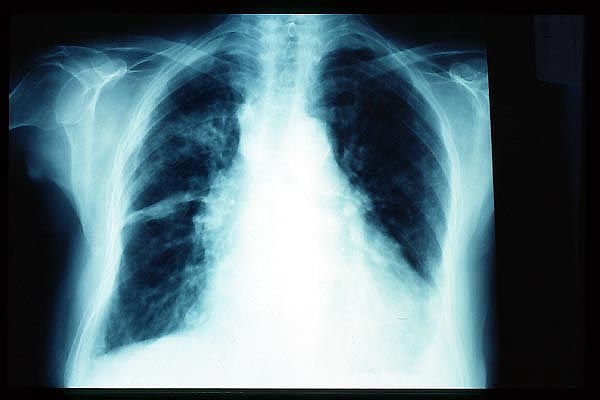

Fibrosis pulmonar. ICC.